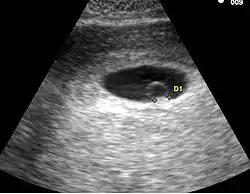

Embryon à 6 semaines

La croissance exponentielle de l'embryon permet très rapidement de le voir. Dès la visualisation de l'embryon une datation précise de la grossesse est possible. En cas de la visualisation de 2 sacs et / ou de 2 embryons, il est impératif de déterminer le type de grossesses gémellaires. Deux situations se rencontrent: